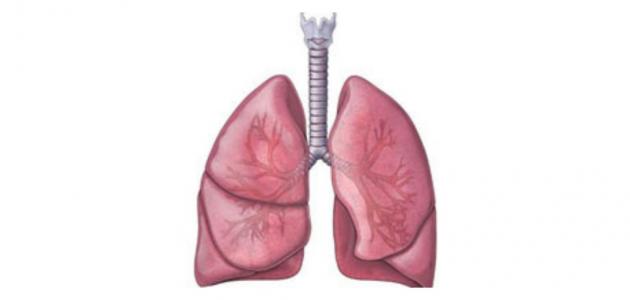

الشعب الهوائية:

وهي شبيهة بالشعيرات الدموية، تبدأ بالتفرع من الحنجرة على شكل أغصان الشجرة ممتدّةً داخل الرئة ووظيفتها نقل الهواء داخل الرئة.

الرئتان:

تقع داخل تجويف القفص الصدري والعمود الفقاري، ويقع تحتها عضلة الحجاب الحاجز، وتحتوي على الشعيرات الدموية الرئوية والقصيبات الهوائية، ووظيفتها تبادل الغازات الناتجة عن عمليات الجسم ففيها يتم تبادل الأكسجين مع ثاني أكسيد الكربون.